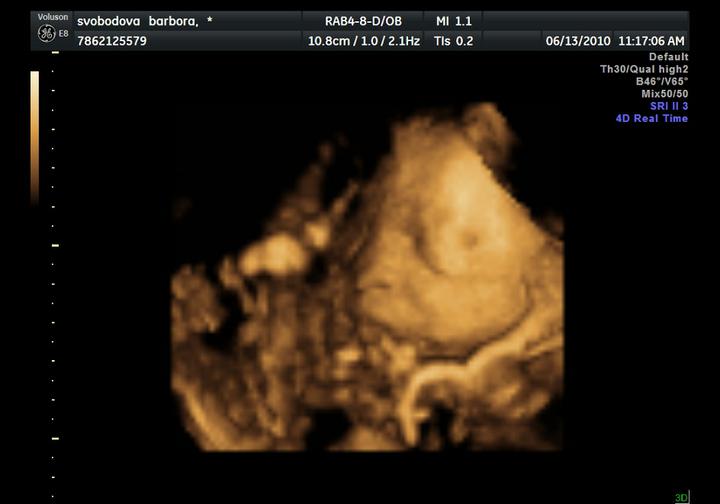

UZ byl naprosto úžasný zážitek, Adámek si cpal ručičky do pusinky, do nosánku, mrknul na nás, a ve finále ukázal fakáče 🙂